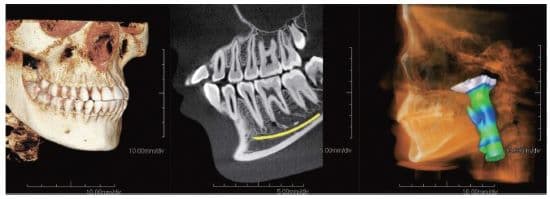

Modern CBCT with innovative semiconductor technology provides exceptional image quality balanced with a low radiation dose to elevate diagnostics and treatment planning

The Expedition features an all-new indium gallium zinc oxide (IGZO) flat panel detector with innovative semiconductor technology, providing superior image quality with less scatter and better detail.

“To diagnose better, we need to see better,” Dr. Kaminer said. “The high-quality images from the Expedition allow us to achieve exactly that.” The system also uses significantly lower power consumption with no image rendering necessary. Its high x-ray tube voltage of 110kV effectively reduces image artifacts, while its high gradation of 16 bits helps to deliver smooth, high-resolution images.

Additionally, the Expedition enables 360° scanning and is equipped with 4 fields of view—5×5 cm, 8×8 cm, and 12.5×10 cm, plus an optional 15×15 cm—covering endodontics to craniofacial treatment.

Clinicians may also benefit from the Expedition’s dedicated 2D panoramic scanning capabilities, or a combination of both 2D and 3D scanning, to ensure a more thorough examination and analysis. Plus, the Expedition is ceph upgradable at any time, affording fast, true 2D cephalometric image acquisition without image rendering in 0.16 seconds.